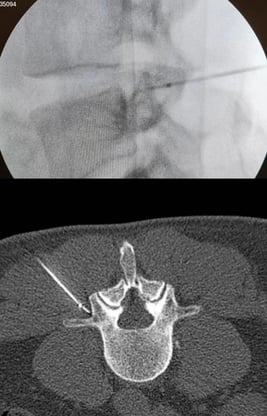

Infiltrações Facetarias

As infiltrações facetárias são um tipo de procedimento utilizado no tratamento de dores crônicas nas articulações vertebrais. Essas dores podem ser causadas por degeneração dos discos intervertebrais ou pela presença de osteoartrite. Durante o procedimento, um medicamento é injetado diretamente nas articulações afetadas, com o objetivo de reduzir a dor e a inflamação. A infiltração facetária pode proporcionar alívio temporário da dor, permitindo que o paciente realize suas atividades diárias com mais conforto. É fundamental que o paciente siga as orientações médicas e busque tratamentos complementares para obter resultados mais duradouros.